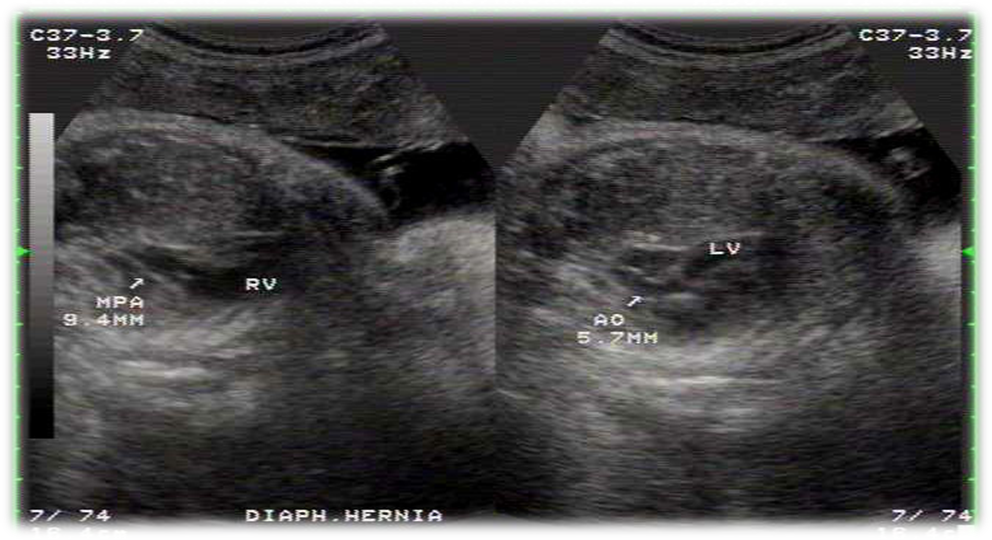

CDH